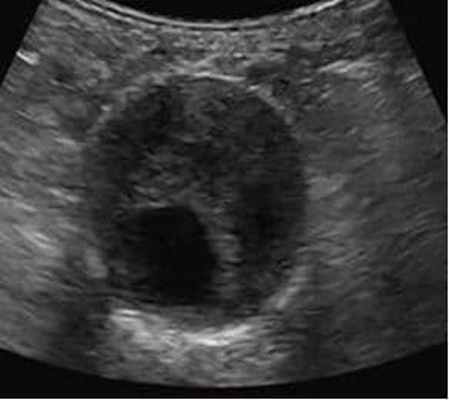

- Ультразвуковое исследование (УЗИ);

Ультразвуковое дуплексное исследование – "золотой стандарт" скринингового обследования пациентов (обнаружение и динамическое наблюдение);

Чтобы диагностировать аневризму брюшной аорты необходимо пройти ультразвуковое исследование (УЗИ) — дуплексное или триплексное сканирование брюшной аорты.